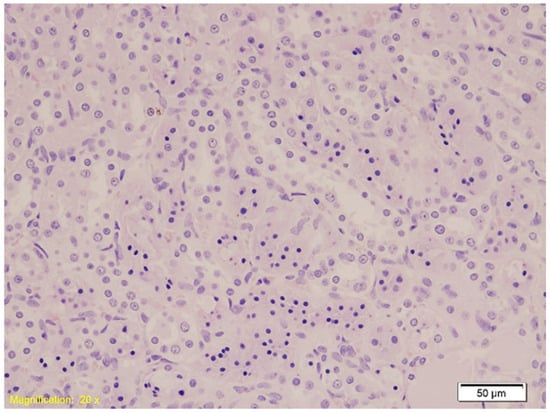

| Kidney | Hydropic and vacuolar degeneration, congestion; occasional acute tubular injury (eosinophilia, swelling, pyknotic nuclei); minimal lymphocytic infiltrate in interstitium. | Similar findings as Group K; occasional acute tubular injury and lymphocytic infiltrate. | Similar findings as Group K; occasional acute tubular injury and lymphocytic infiltrate. |